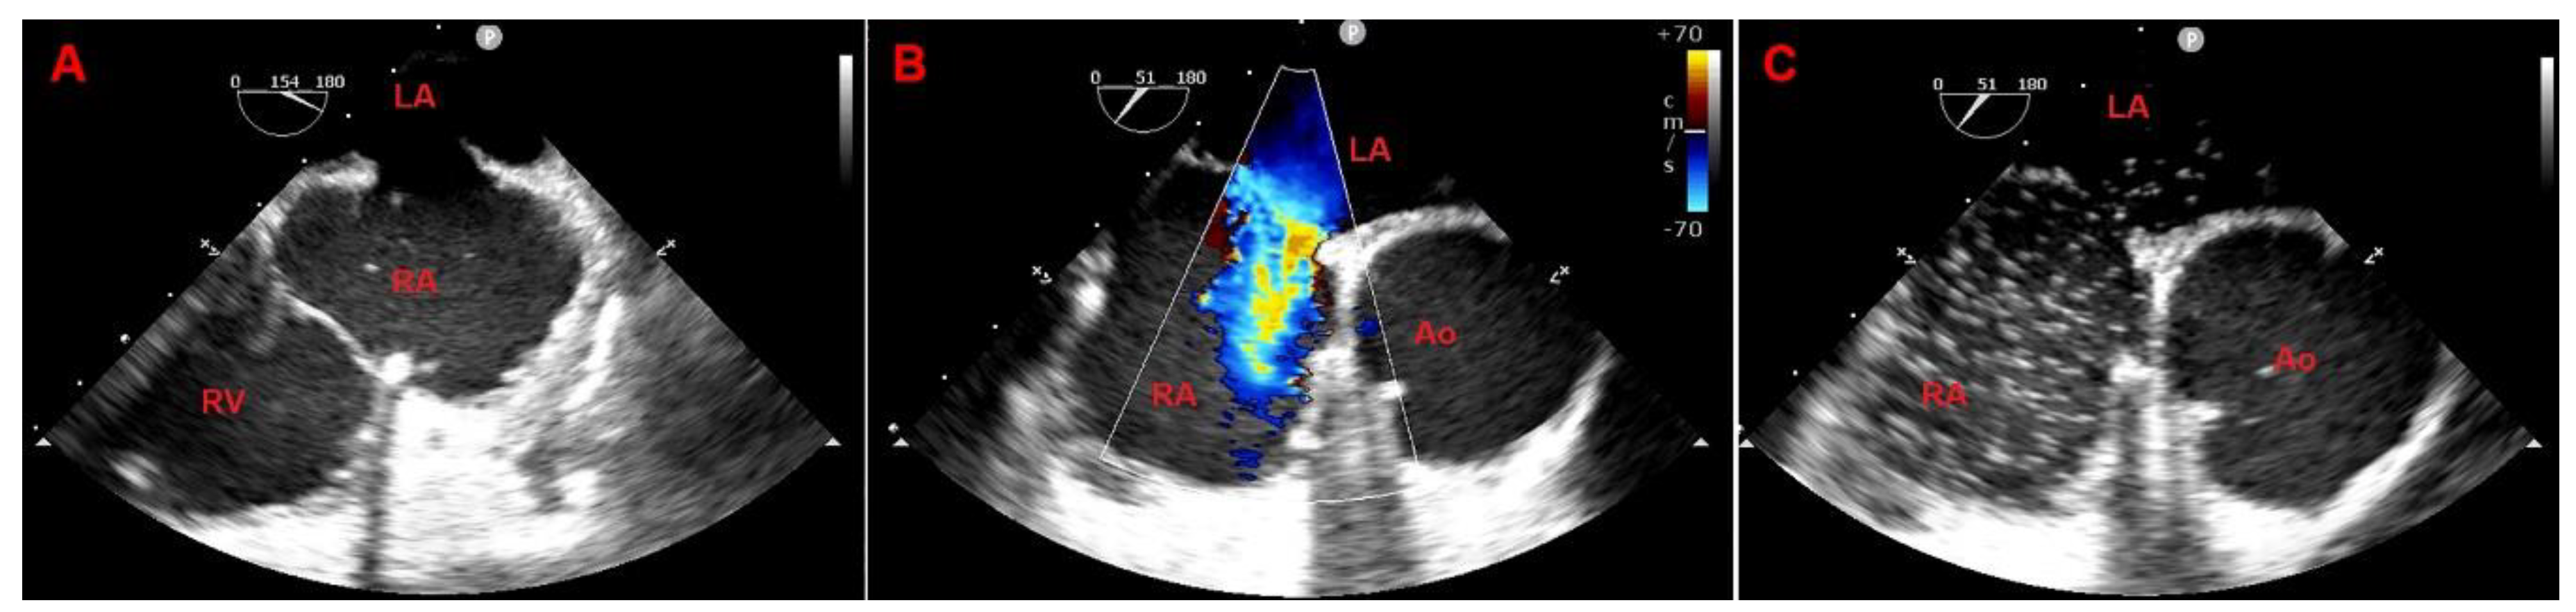

A TTE confirmed good surgical outcome showing mitral valvuloplasty with good leaflet dynamics with only minimal residual regurgitation and tricuspid valvuloplasty without residual regurgitation, normal LV with post-surgery septal dyskinesia, LVEF equal to 50%, normal atrial and right ventricle size with post-operative reduction of systolic longitudinal function and no pericardial effusion. Of note, TTE showed dilatation of inferior vena cava without collaps during breathing and a significant bi-directional shunt (left-to-right prevalent) due to a large ostium secundum type atrial septal defect (ASD)(diameter = 15 mm) with ratio between pulmonary (Qp) and systemic flow (Qs) equal to 1.5 in basal conditions (Figure 1).

The post-operative phase was regular. The TTE showed a good outcome of mitral and tricuspid valve repair and a stable closure of the atrial septum (even when tested with microbubbles) (Figure 3).

Figure 1. Two-dimensional TTE showing ostium secundum type ASD causing significant bi-directional (left-to-right prevalent) at color Doppler. (A) apical four-chamber view, (B) parasternal short axis view at the level of aortic valve, (C) sub-costal four chamber view.

Figure 3. Two-dimensional TTE showing the absence of interatrial shunt after surgical correction of ASD. (A) apical four-chamber view, (B) parasternal short-axis view at the level of aortic valve, (C) sub-costal four-chamber view.